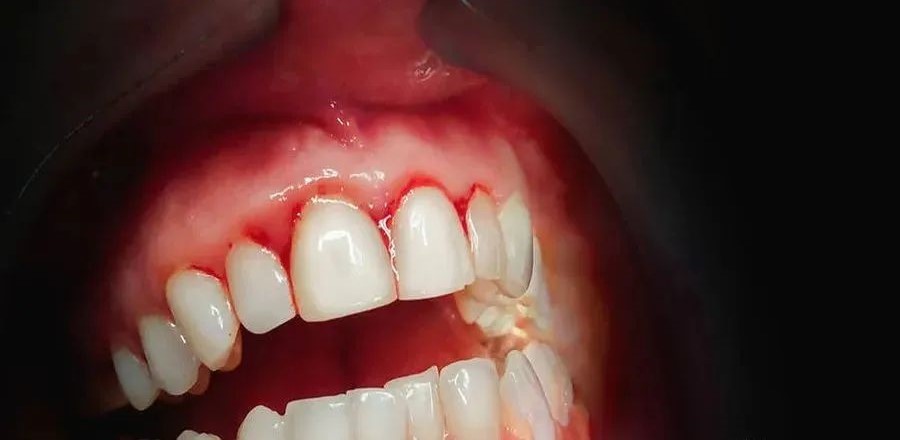

1、刷牙或者咬硬物时牙龈出血:正常的牙龈是不应当出血的,许多人认为牙龈出血是身体上火,买个败火的牙膏刷牙或者吃点败火的药就可以了,实际上,牙龈出血是牙周炎早期的症状之一,是机体发出的信号,告诉你牙龈发炎了,如果你不重视这个信号,那么牙周炎就会继续发展下去。